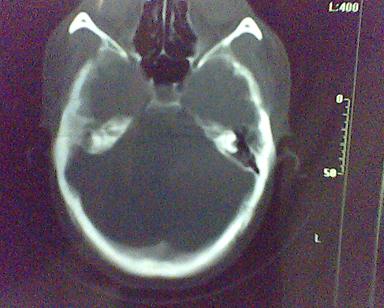

男 31岁 短暂性四肢抽搐 呼叫不应  头胀痛4个多月 无发热 4年前遭棒击头部,当时未到医院检查。余无特殊。病人特穷,未作增强。

右侧乳突蜂房消失,右侧颞叶区囊性占位,水肿不明显,考虑表皮样囊肿或耳源性脑脓肿,+c!。

首先考虑耳源性脑脓肿。